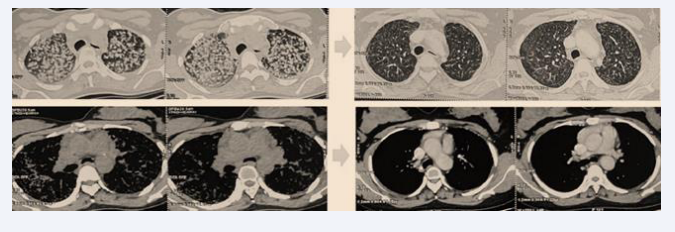

After two months of corticosteroid therapy, the patient showed significant improvement, with reduced dyspnea, disappearance of cough and anxiety, resolution of crackles, and a weight gain of 15 kg. At six months, dyspnea and crackles had completely disappeared, and the patient resumed her daily activities, including work. ACE levels showed a significant decrease (96 U/L vs. 192 U/L), and the six-minute walk test revealed normal oxygen saturation in ambient air (SpO? = 99%) after walking 280 meters without dyspnea. Follow-up chest CT showed a marked regression of nodules, micronodules, and hilar and mediastinal lymphadenopathy (Figure 5).

Figure 5 Follow-up chest CT showing significant regression of nodules, micronodules, and hilar and mediastinal lymphadenopathy.

Figure 5: Follow-up chest CT showing significant regression of nodules, micronodules, and hilar and mediastinal lymphadenopathy.